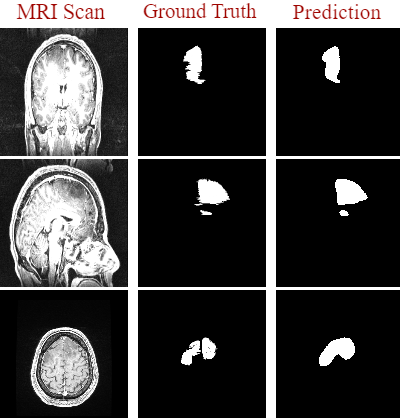

Training the network began in small iterations where we monitored the segmentation performance based on iterations alone. Early results using 101010 epochs produced poor results across two of the image planes notably the sagittal and coronal planes. Poor segmentation results were expected based on the small epoch range used during training, however, adequate results were recorded on the transversal plane. This is likely due to the size of each dataset as the transversal dataset had the most images as the patient’s tumor is most prominent from this particular perspective. To further improve these results we increased the networks epoch range to 505050 and monitored the results to see if the segmentation performance had improved. Using 505050 epochs significantly improved the networks segmentation performance across all three perspective planes. Figure. 5 shows the results across all three perspectives using only 505050 epochs and the proposed network architecture from Section 4.1. Here, model 1 (or first model) is the standard U-Net architecture, whereas the model 2 (or the final model) is the proposed U-Net with optimized filter values.

Refer to caption

Figure 5: Segmentation results recorded using U-Net with 50 epochs.

Several algorithms were chosen to benchmark to further evaluate the segmentation performance obtained using U-Net. These algorithms specified in Section 2 of the paper were chosen based on their success on biomedical image segmentation. Each algorithm was used to compare our segmentation results obtained using our proposed model. Each algorithm was tested using the extracted test sets of each of the four available datasets. Figure 8 shows the three ground truth images which correspond directly to the predictions generated in Figure 9.

Figure 8: The ground truth images used to evaluate our chosen benchmarking algorithms.

Comparing the results obtained using U-Net to those obtained to benchmark, we observed that our proposed model outperformed each of these benchmarking algorithms. While the deep learning methods perform segmentation task automatically, the other three benchmarking algorithms (Thresholding, K-Means, Fuzzy C-Means) needed more ‘manual’ interference. They perform better when the tumor is clearly distinguishable at the pixel level in terms of intensity and isolation. This also means that to achieve maximum performance when the parameters are fine-tuned separately for each image, which essentially renders the whole process useless. The three-manual segmentation algorithms were implemented for automatic segmentation of brain tumors from MRI images. However, these algorithms are not fully automatic and may require fine-tuning for good results. Thus, a lightweight deep-learning architecture which can provide real-time automatic segmentation of brain tumors is needed.

Figure 9: Comparison of the results obtained during the benchmarking process to those predicted via U-Net.

More promising results came from LinkNet which can be observed in Table 3 below. The implementation of LinkNet was consistent with the original architecture used when it was first proposed. However, small changes were made to the network to suit our segmentation goal. These small changes were simply related to the particular activation function used at the final layer of the network. Also, the common loss function for multi-class segmentation problems, which was originally used (i.e. categorical cross-entropy), was changed. Visual predictions generated using LinkNet were adequate. However, the performance fluctuates as the perspective of the image changes, for instance in Figure. 9 on the coronal and sagittal plane we observed mixed results as the network successfully captures the location of the tumor but cannot directly generate its size or structure. Whereas on the transversal plane, comparing the generated prediction with its corresponding ground-truth from Figure. 8, we observe an increase in segmentation performance as the prediction is very accurate. This performance increase is likely due to the size of the dataset as the transversal plane contains more images than both the coronal and sagittal planes combined.